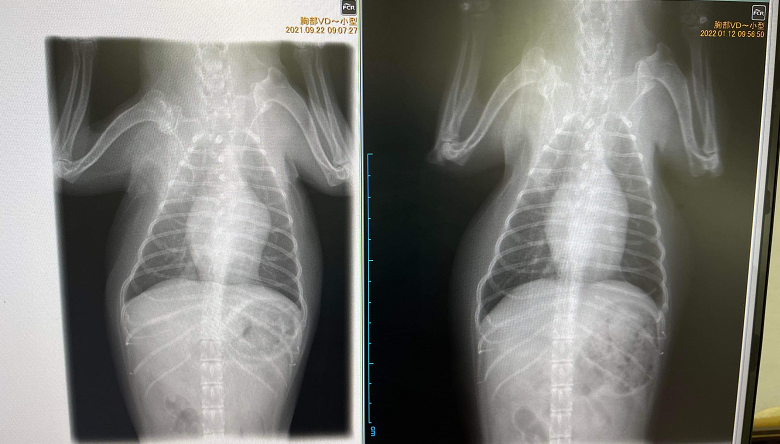

10月から「月のしずく」と「神秘の水 夢」を飲ませて、3ヶ月で心臓の肥大が少し小さくなり、肺の白い影が薄くなりました。

レントゲン写真撮ってきたので参考までに送ります。

微妙ですが変化してることがわかると思います。左が昨年9月、右が今年1月です。